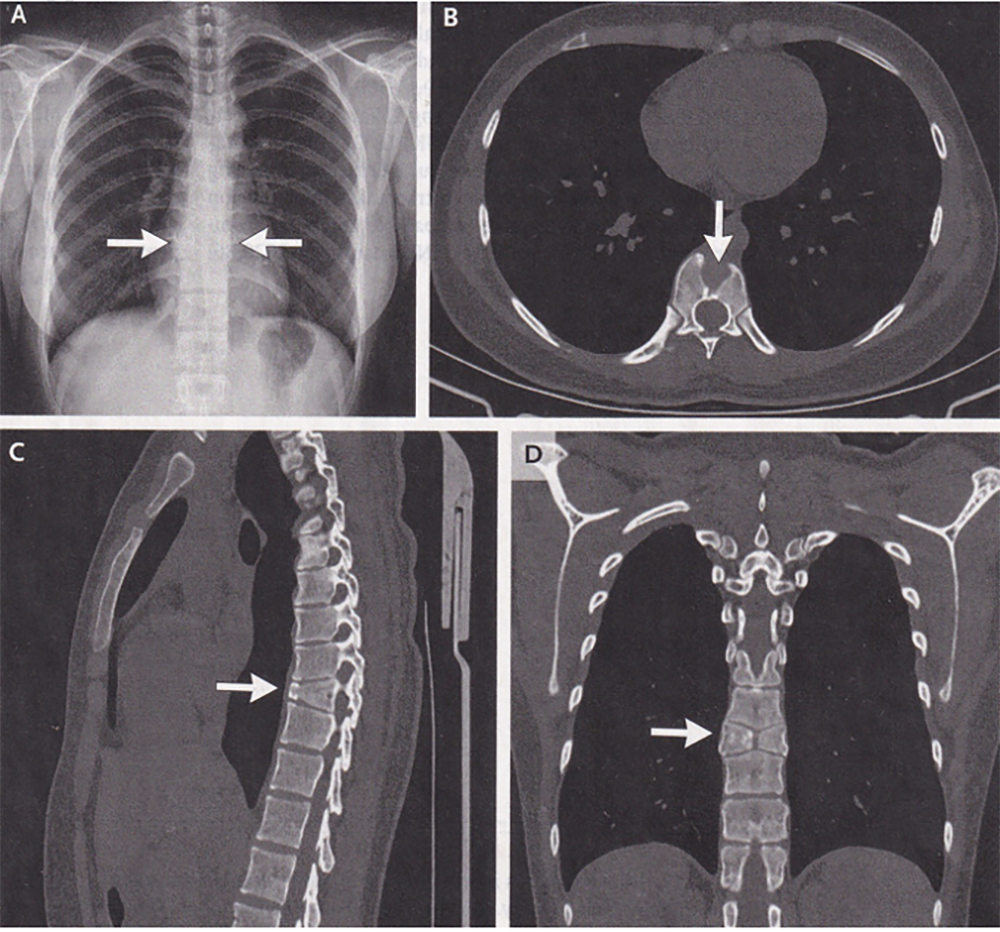

A 21-year-old woman presented to the pulmonary clinic at the Fourth Affiliated Hospital of China Medical University in Shenyang, China with a seven-day history of sore throat and cough. On routine chest X ray, she was noted to have a spinal abnormality. She denied a history of back pain. Physical examination was notable only for mild pharyngeal erythema (throat redness). The X ray showed normal lungs and two hemivertebrae (Panel A, arrows) at the ninth thoracic vertebral body (T9). A subsequent CT scan of the chest showed a sagittal cleft (Panel B, arrow). The sagittal plane runs from head to toe and divides the body into right and left sides. The CT also showed anterior wedging (Panel C, arrow) on the parasagittal view (from the side). On the coronal view (from the front), it showed symmetric, triangular hemivertebrae resembling the wings of a butterfly at T9 (Panel D, arrow). A diagnosis of butterfly vertebra was made.